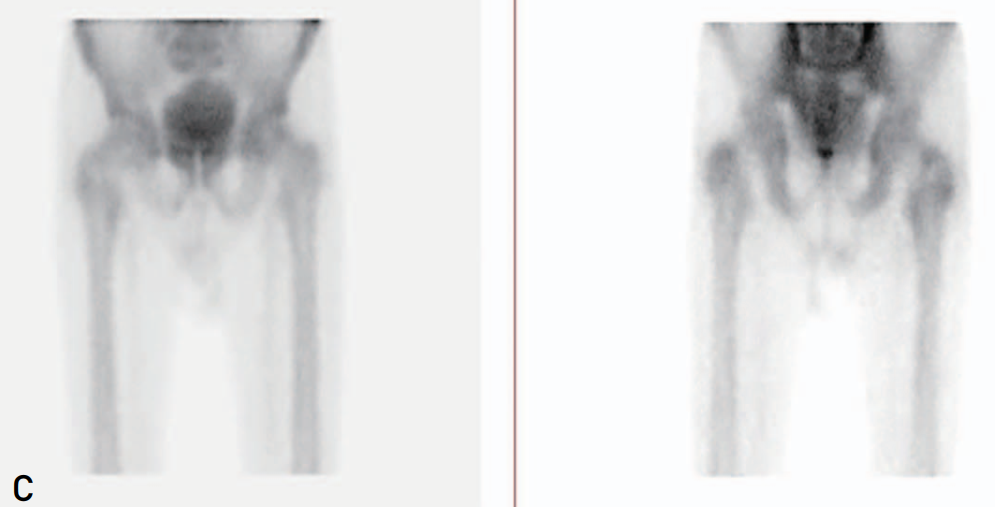

▲图示可见右侧转子间骨折线仅累及外侧1/2骨质,行保守治疗。

▲图示可见做侧转子间骨折线累及整个大小转子间骨质,且累及股骨颈基底部。